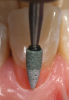

Among the armamentarium required for creating direct composite pink prosthetic restorations are pear-shaped diamonds for carefully cutting the micro box (Figure 5 and Figure 6) and a marginator fine flame diamond (ie, very small inverted cone diamond bur) to create undercuts or micromechanical retention (Figure 7 and Figure 8). Note that there is no radius beveling at the gingival margin; a butt joint is created that will require sealing.

Fig 5. The smallest pear-shaped diamond was used with water to carefully cut the rough boundaries of the preparation.

Figure 5